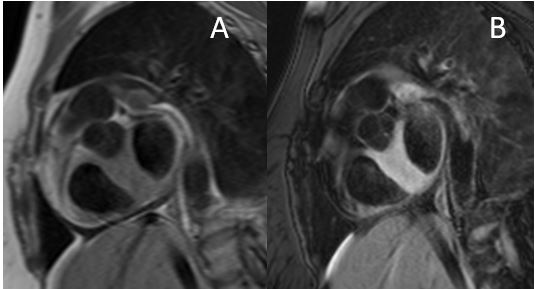

Figure 3: Four chamber (A) and Short Axis (B) late gadolinium enhancement